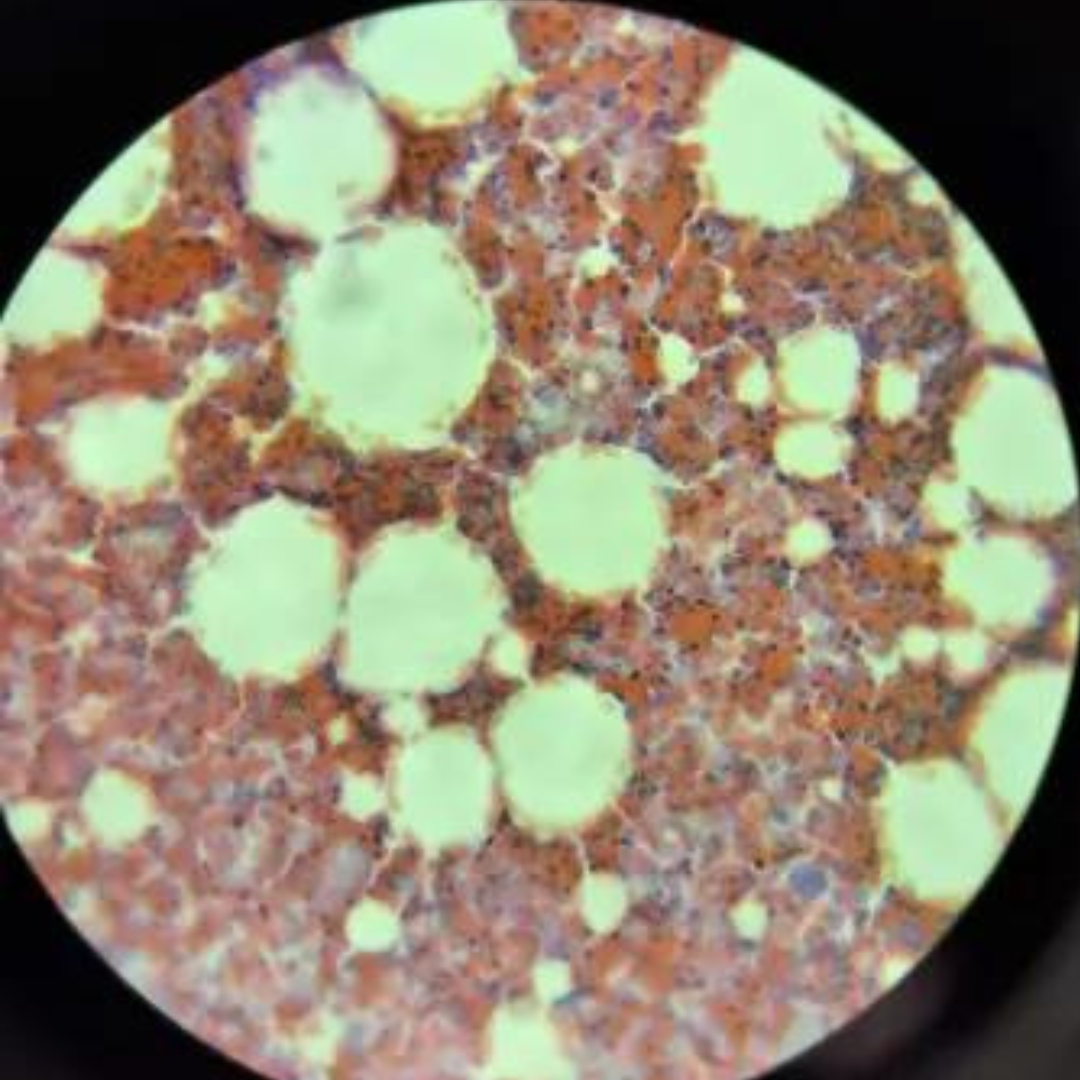

4

New cards

Blood

5

New cards

Bone Marrow

6

New cards

Bone Marrow